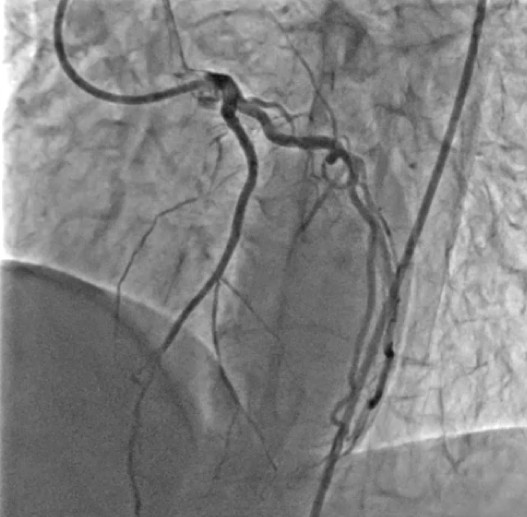

- Well-developed septal-to-septal collateral channels connecting the proximal septal branch of the LAD or LCX to distal LAD septal branches were identified and deemed suitable for retrograde approach.A Sion wire was advanced into the donor septal branch through the same guide catheter. Over the wire, a Corsair Pro XS microcatheter was carefully navigated through the septal collateral to reach the distal true lumen of the LAD, under fluoroscopic roadmap guidance

- Using a Gaia Second wire, the CTO segment was crossed retrogradely from the distal LAD into the proximal true lumen of the LAD.

- The retrograde wire was maneuvered into the antegrade guide catheter through the subintimal space.Sequential balloon dilatation was performed to prepare the occluded segment.Overlapping drug-eluting stents (DES) were deployed to cover the entire length of the CTO.Final angiography demonstrated TIMI 3 flow in the LAD with no residual stenosis or complications.